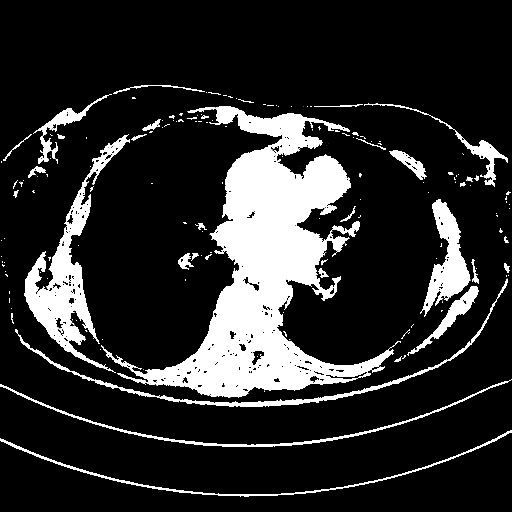

Reconstructed NATIVE CT scan (cycle consistency)

Full window (WL 1023.5, WW 4095 β†’ Low βˆ’1024, High +3071)

Actual HU range: [-1024.0, 3071.0]